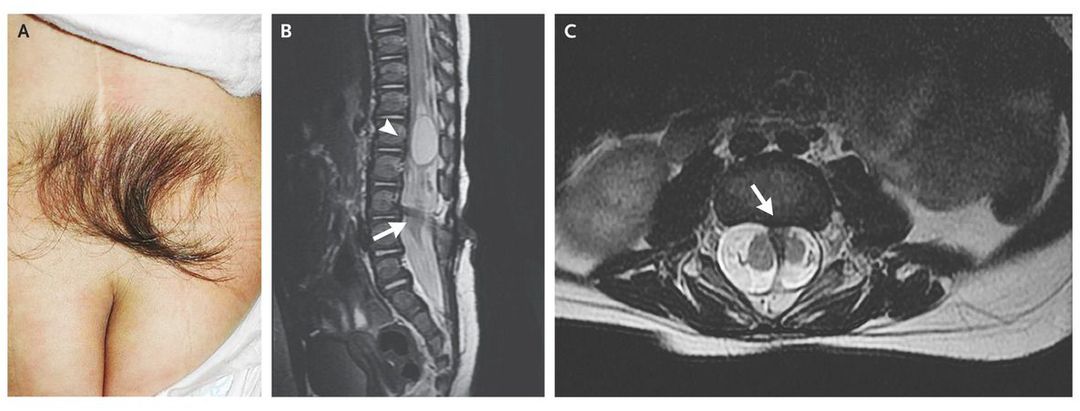

A 3-year-old girl was referred for the removal of excess hair on the back, which had been present since birth, for cosmetic reasons. The physical examination revealed a tuft of coarse, dark hair in the midline of the back just above the natal cleft (Panel A). Her history revealed leakage of clear fluid from the hypertrichotic region since birth. At that time, magnetic resonance imaging had shown syringomyelia at L1 (Panel B, arrowhead), diastematomyelia with bony spurs at L3 and L4 (Panel C, arrow), and tethered cord and low-lying conus medullaris at L5 (Panel B, arrow). At the age of 4 days, the patient had undergone repair of leakage of cerebrospinal fluid, and at 7 months of age, she had undergone drainage of the syrinx, release of tethered cord, and removal of bony spurs to repair the diastematomyelia. In the 3-year follow-up after surgery, the patient had had no leakage of cerebrospinal fluid, no urinary or stool incontinence, no difficulty in walking, and no developmental delay. The histopathological examination of a specimen of cerebrospinal fluid that had been obtained during the first surgery was compatible with meningocele. A patch of hair in the lower back may be a cutaneous marker of spinal dysraphism and should prompt consideration of underlying spinal abnormalities to prevent neurologic sequelae. The parents were informed about the laser technique for removing excess hair when the child is old enough to cooperate with the procedure.